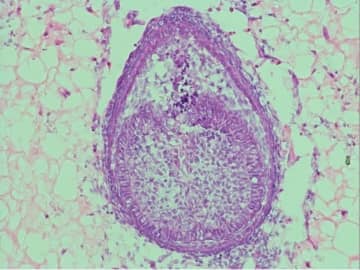

ヒトの歯を培養する研究、実用化に向け前進 (CNN) 英キングス・カレッジ・ロンドンの再生歯科大学院課程の責任者アナ・アンゲロバ・バルポーニ氏... CNN.co.jp | Fri, 24 Oct 2025 16:59:22 +0900 もっとよむ Pick Up 2025年10月09日 「ちみたん× 選べるニュース」のLINEスタンプを無料でGET! チバテレ+プラス ライフ 2024年03月07日 【新商品!】チュバチュバワンダーランドに新たなグッズが登場★ チバテレ+プラス ライフ